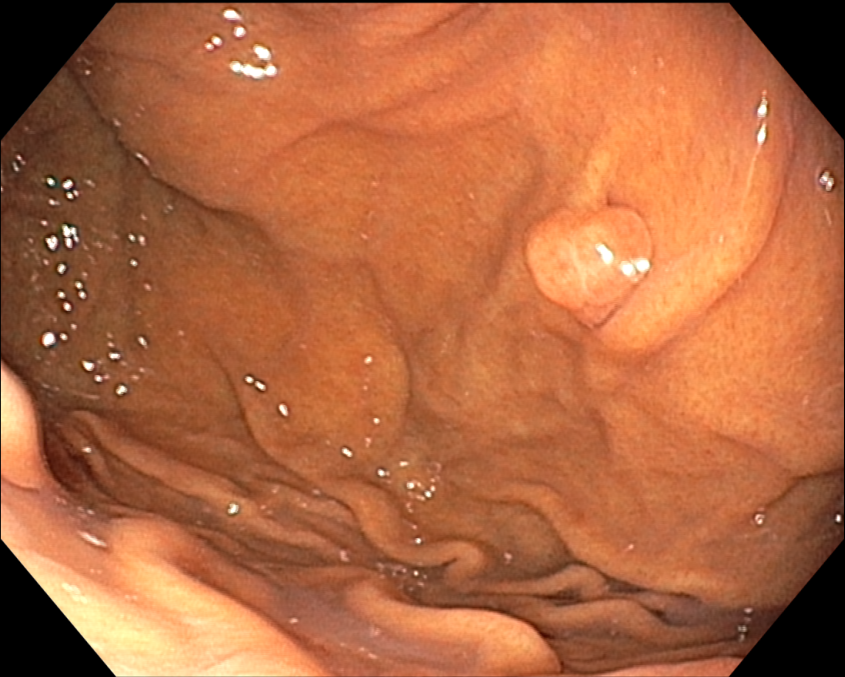

D Fundic gland polyp이고 제거할 필요가 없습니다.

Fundic gland polyp의 악성 잠재성 (malignant potential)은 없습니다. Somatic APC gene mutations이 dysplasia가 없는 syndromic fundic gland polyps의 70 % 이상에서 발견되었으나 sporadic lesions에서는 10 % 미만이었습니다. Sporadic fundic gland polyps과 PPI와 관련된 polyps은 실질적으로 악성 잠재성이 없습니다. 그러나 dysplasia가 드물게 있기도 합니다. FAP 환자의 fundic gland polyps의 경우 30-50%는 dysplasia를 나타내지만 전형적으로는 low grade입니다. 그러나 FAP 환자에서의 adenoma와 대조적으로 fundic gland polyps은 거의 암으로 진행하지 않습니다. Fundic gland polyps은 빈번하게 다발성이고 한 개 이상 대표적인 몇 개의 조직검사로 충분합니다. 남은 polyps은 내시경으로 주의 깊게 (?) 관찰하고 다른 곳과 달라 보이는 polyps은 조직검사를 하고 가능하면 제거합니다. 1 cm 이상의 polyps, 궤양이 있는 poylps, antrum에 있는 polyps은 절제해서 dysplasia는 없는지 neplasia는 없는지 확인해야 합니다. |

Familial polyposis syndrome 가능성은 poyps이 20개 이상인 경우, antrum에 fundic gland polyps이 있는 경우, 젊은 나이 (40세 이전)에 발생한 fundic polyps, 십이지장에 adenoma가 동반된 경우에 고려되어야 하고 대장내시경을 시행해야 합니다. PPI 사용으로 여겨지는 sporadic fundic gland polyps 환자에서 polyps이 20개 이상이거나 1cm보다 큰 경우에는 PPI를 중단합니다. 이와 같은 환자에서 hypergastrinemia는 gastrinoma (Zollinger-Ellison syndrome) 또는 좀 더 일반적으로는 PPI-induced hypochlorhydria를 시사하고 존재한다면 PPI 용량을 줄이거나 중단합니다. 만일 GERD 치료를 위해 위산 분비 억제가 필요하고 H2R blocker로 치료되지 않으면 가장 낮은 용량으로 다른 PPI를 고려합니다. |